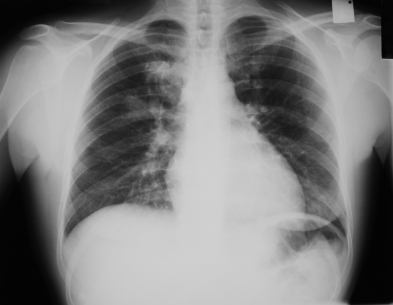

Аорты является большой артерии, которая возникает из крови сердца и поставок на весь организм. Аортография является исследование аорты с помощью рентгеновских лучей после введения контрастного вещества.

Типичные осложения:Повреждение артерии во время введения контрастного вещества. Контраст редко могут повредить почки и у некоторых пациентов может быть аллергическая реакция на краску. Аллергическая реакция может быть легкой до угрожающей жизни.